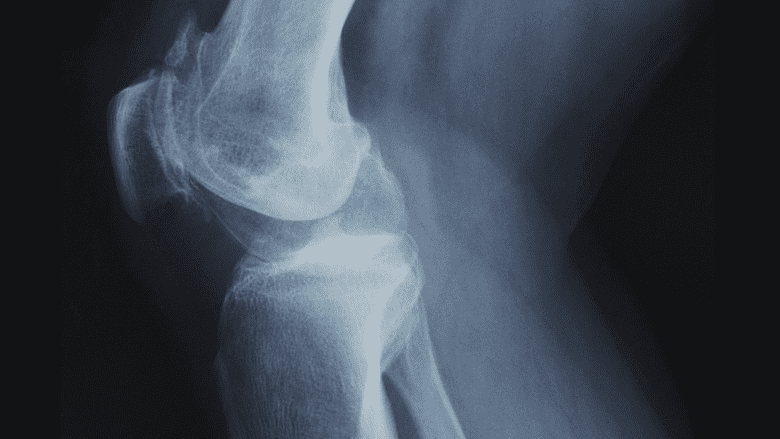

X-ray imaging may be used to diagnose a knee cap dislocation and determine the severity of the injury.

Imaging will play a large role in diagnosing a kneecap dislocation, determining the severity of the injury, and developing a treatment plan. Two common imaging methods may be used:

- X-Ray. This type of imaging allows a physician to gain a clear picture of the bone structure of the knee joint. In severe dislocations, the swelling may be so intense that the kneecap cannot be located without an X-Ray. An X-Ray can also be used to determine if there was any break or fracture sustained by the kneecap during the dislocation.